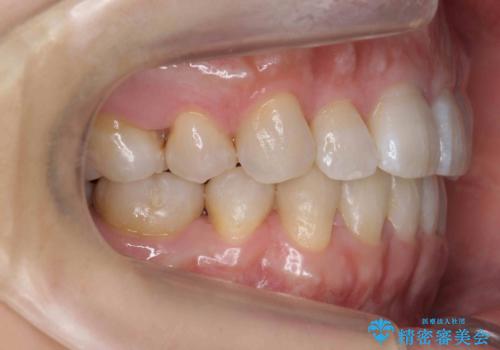

矯正治療で右下を抜歯し、スペースを天然の歯でつめる矯正治療を行いました。

治療期間はかかりましたが、右下4が一生もつとは思えない状態でしたので、人工物を入れないようにすることができました。

矯正治療をしない場合は、右下はブリッジかインプラントが必要になっていたと思います。

上顎前歯も唇側傾斜しておらず、もともと叢生が多くない状態で上下左右を抜歯した上、リンガルで治療を行なったため、多少治療期間がかかりました。